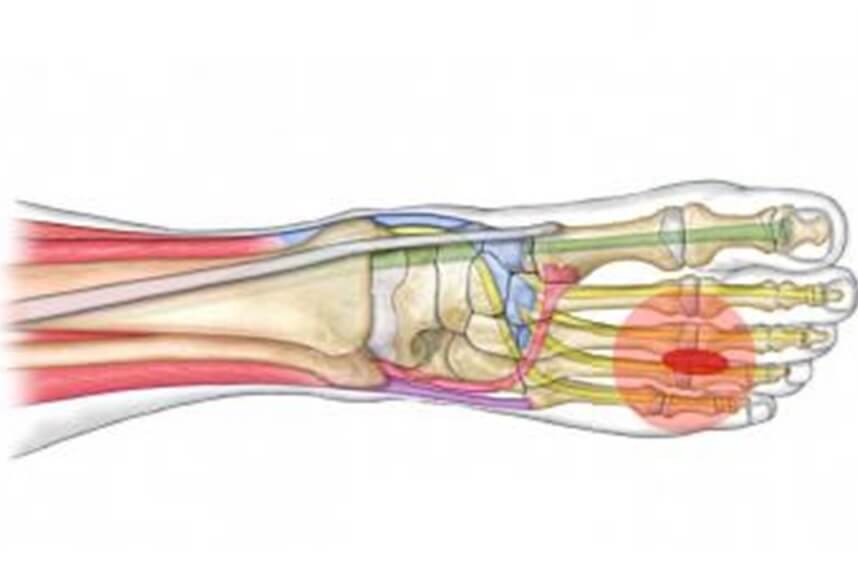

Neuromul lui Morton

Neuromul lui Morton este adesea atribuita tumefierii in ramurile nervului plantar care se afla intre al doilea si al treilea, respectiv al treilea si al patrulea metatars. Compresiunea acestor nervi intre capetele metatarsiene poate fi cauzata de microtraume care rezulta din utilizarea incaltamintei neadecvate (pantofi ingusti in special).

Pacientii prezinta de obicei un debut brusc al durerii, de multe ori comparat cu un soc electric. Amorteala este de asemenea, in mod frecvent prezenta in cele doua degete afectate.

Diagnosticul este in esenta clinic, dar poate fi confirmat printr-o ecografie sau o scanare RMN. Tratamentul initial este conservator, dar in cazurile severe, unde este necesara interventia chirurgicala, neuromul este eliminat.